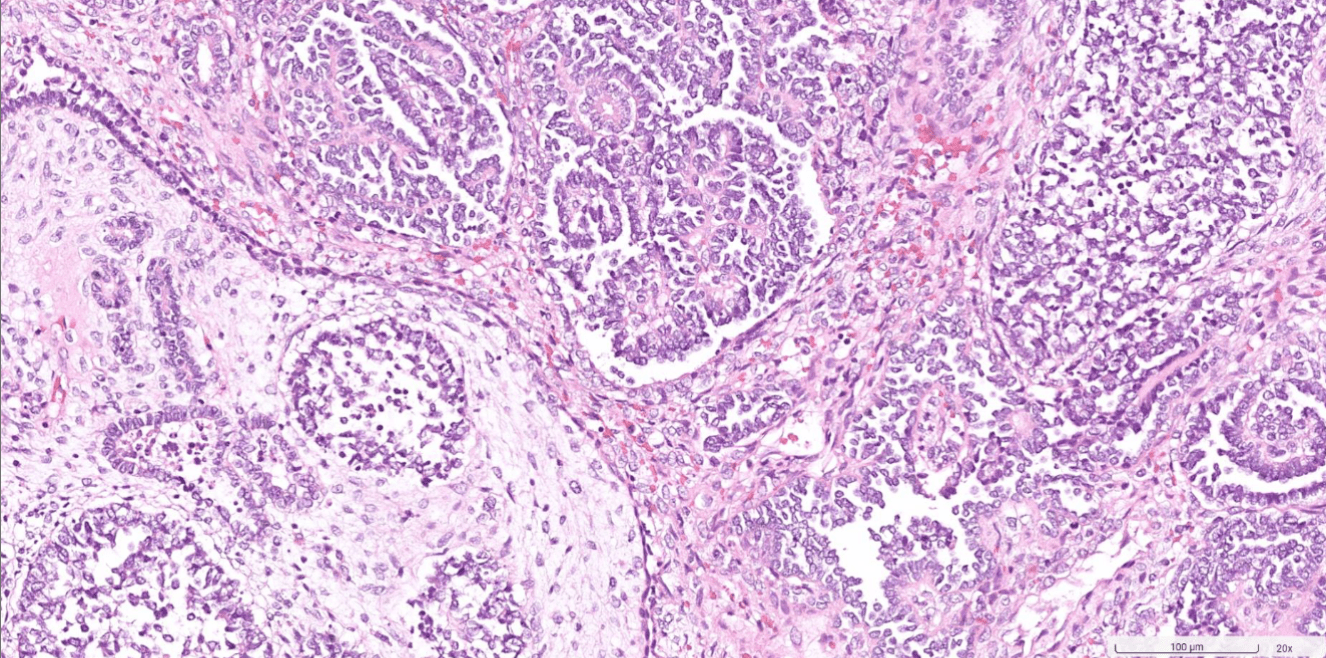

endometrial cancer